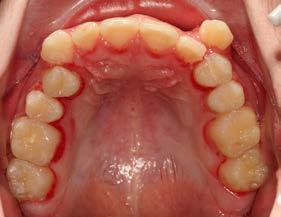

Análisis intraoral de inicio

Las fotografías intraorales muestran las relaciones molares clase II y las relaciones caninas clase II bilaterales (Figura 3 y 4), espaciamiento anterosuperior, un overjet y overbite aumentado (Figura 5). La forma de los arcos es cuadrada, superior e inferior, con el apiñamiento moderado inferior y los espacios en superior.